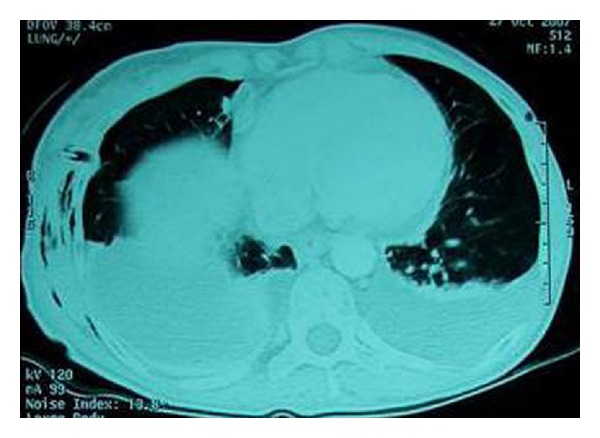

A 45-year-old woman was referred to our department with complaints of high-grade fever and progressive shortness of breath. The patient had undergone diagnostic right ureteroscopy for recurrent renal colic at a different centre one week ago. She had a history of gastrectomy due to gastric carcinoma three years earlier, with subsequent chemotherapy and irradiation. There was no past history of pulmonary or heart disease. On clinical examination, the patient was febrile with a high respiratory rate. Chest radiograph showed massive pleural effusion on the right side (Figure 1) and chest CT (computed tomography) confirmed the diagnosis revealing bilateral pleural effusion (Figure 2). The patient was emergently managed with right closed pleural drainage. Biochemical evaluation of the drainage fluid indicated that it was urine. IVU (intravenous urography) and abdominal CT demonstrated retroperitoneal urine accumulation. This was a possible iatrogenic complication during the previous ureteroscopy. After the subsiding of the respiratory symptoms this urine collection was further treated with percutaneous nephrostomy and drainage of the retroperitoneal space. The chest tube was removed on the fourth day without recurrent effusion.

Figure 2.

Case 1: CT scan revealing extensive bilateral pleural effusion.